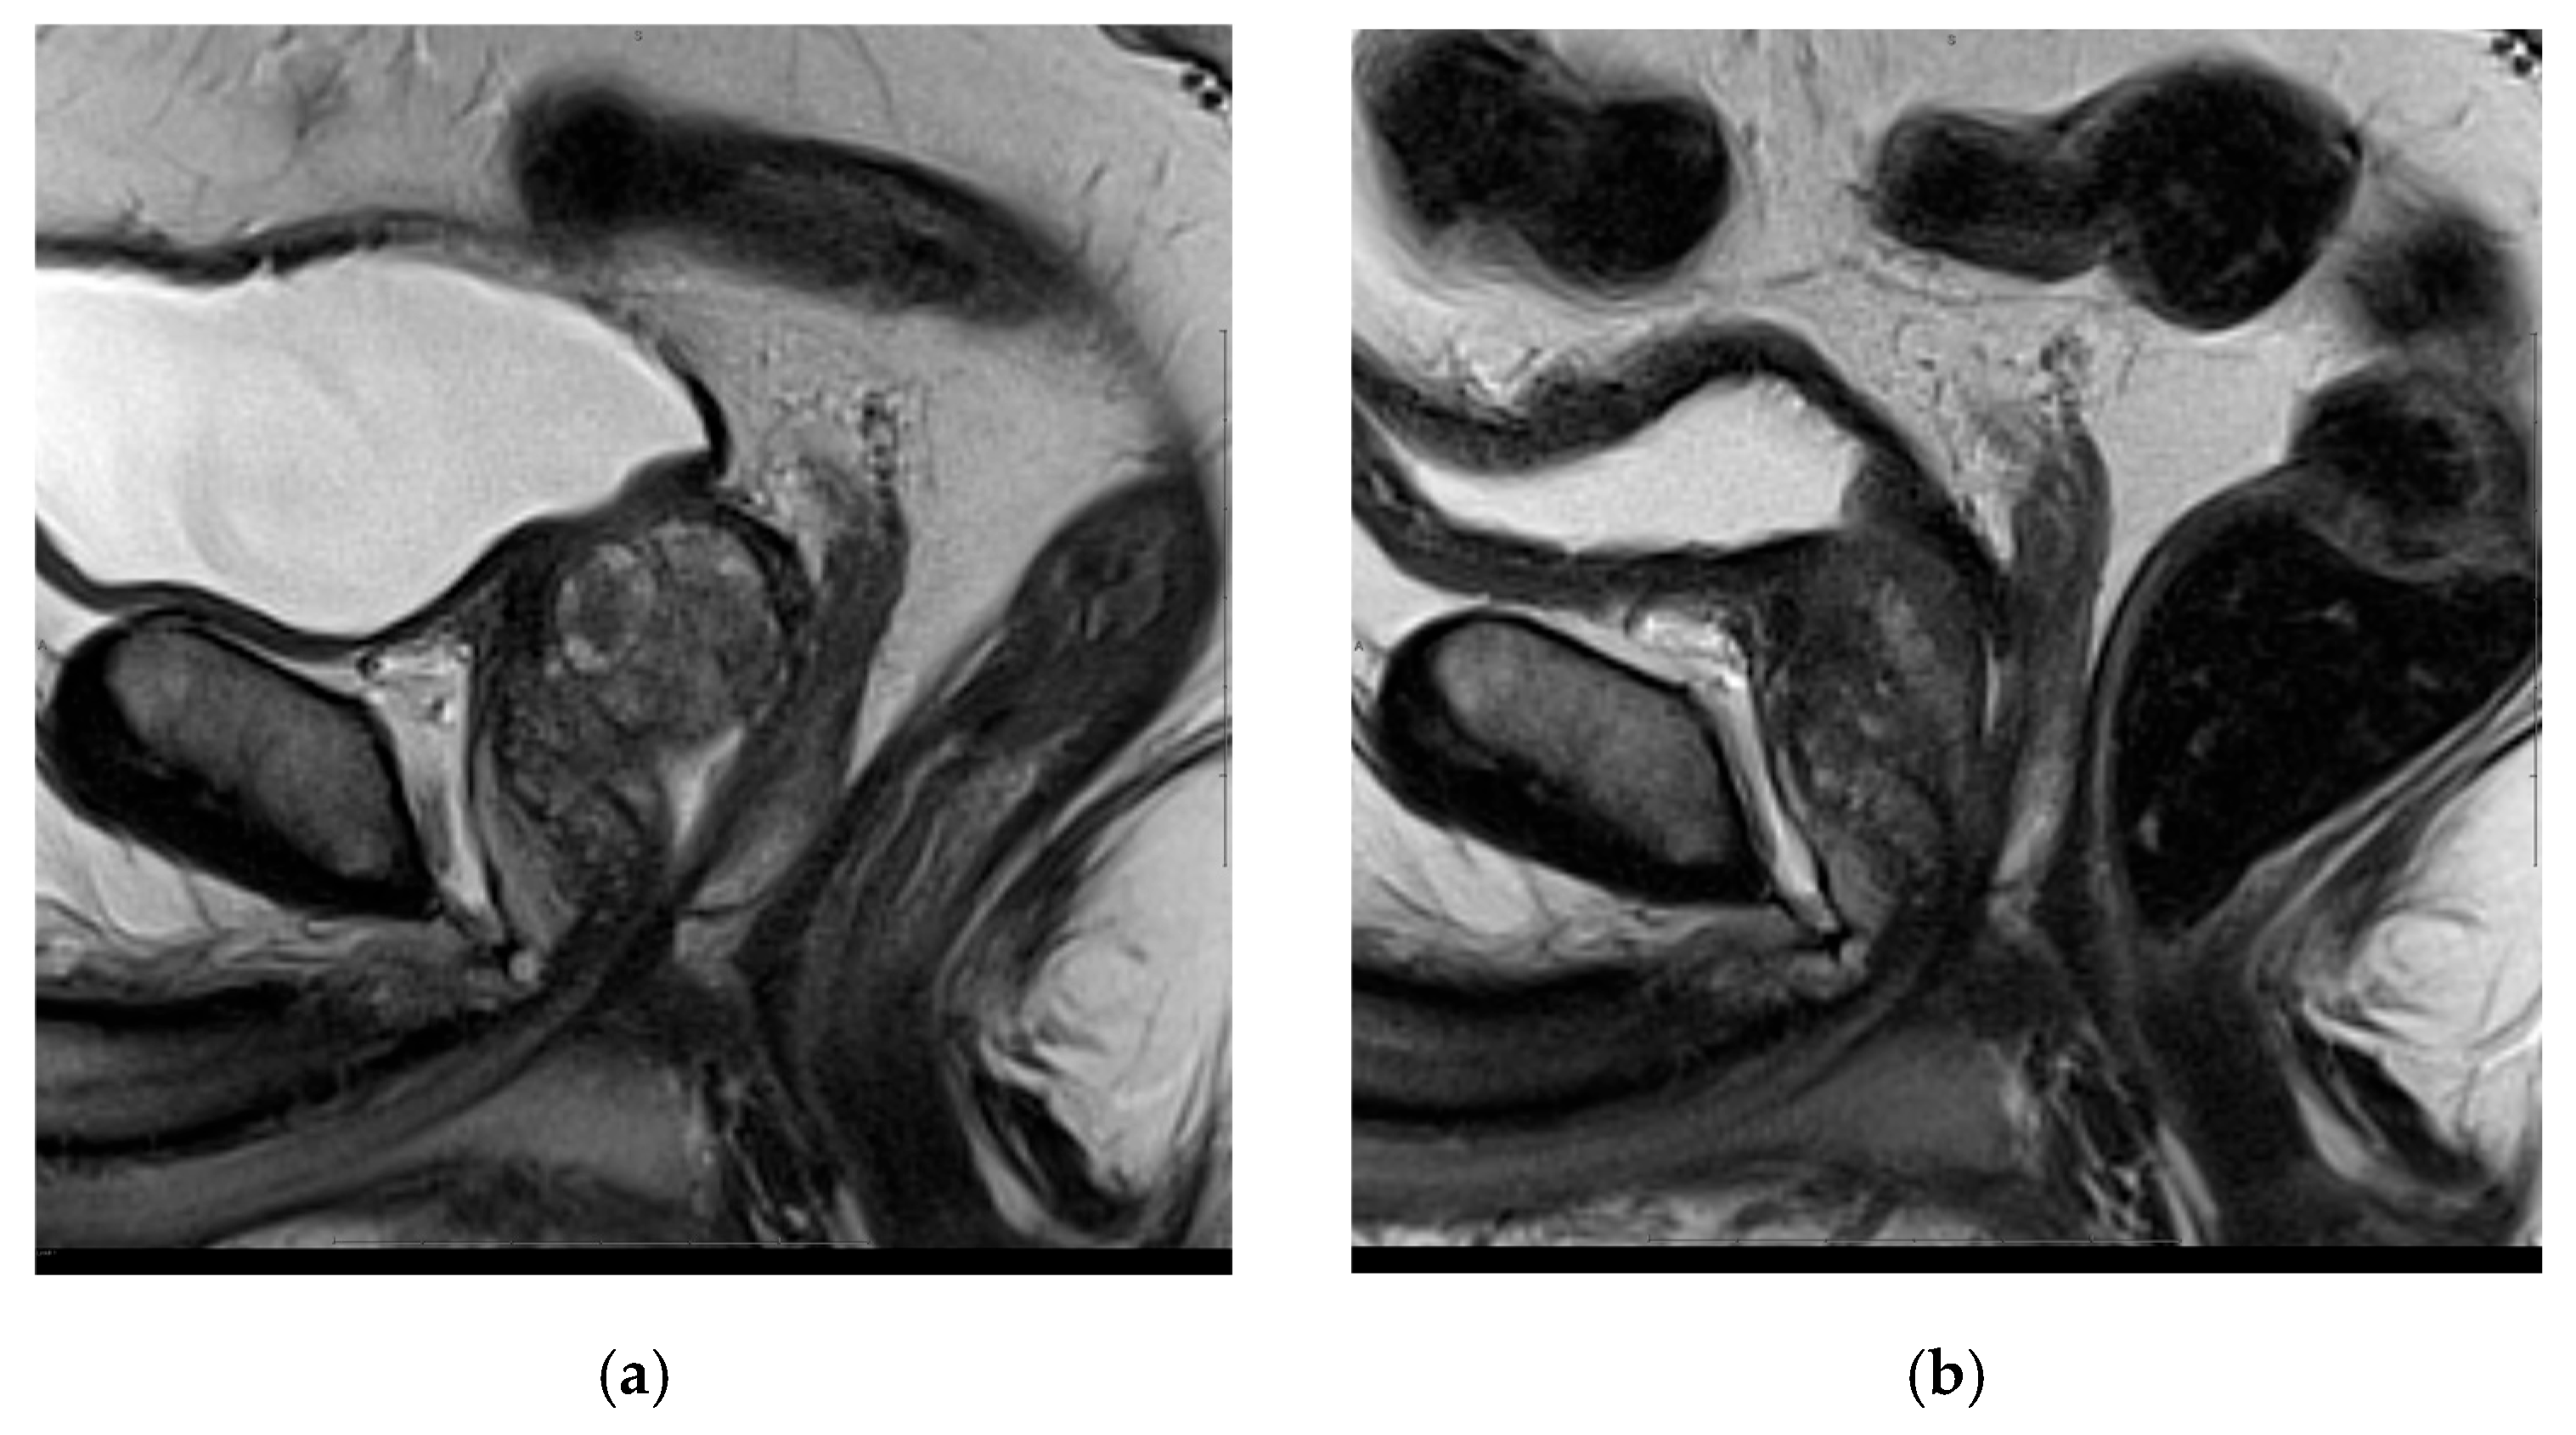

- Manenti, G.; Perretta, T.; Calcagni, A.; Ferrari, D.; Ryan, C.P.; Fraioli, F.; Meucci, R.; Malizia, A.; Iacovelli, V.; Agrò, E.F.; et al. 3-T MRI and clinical validation of ultrasound-guided transperineal laser ablation of benign prostatic hyperplasia. Eur. Radiol. Exp. 2021, 5, 41. [Google Scholar] [CrossRef] [PubMed]